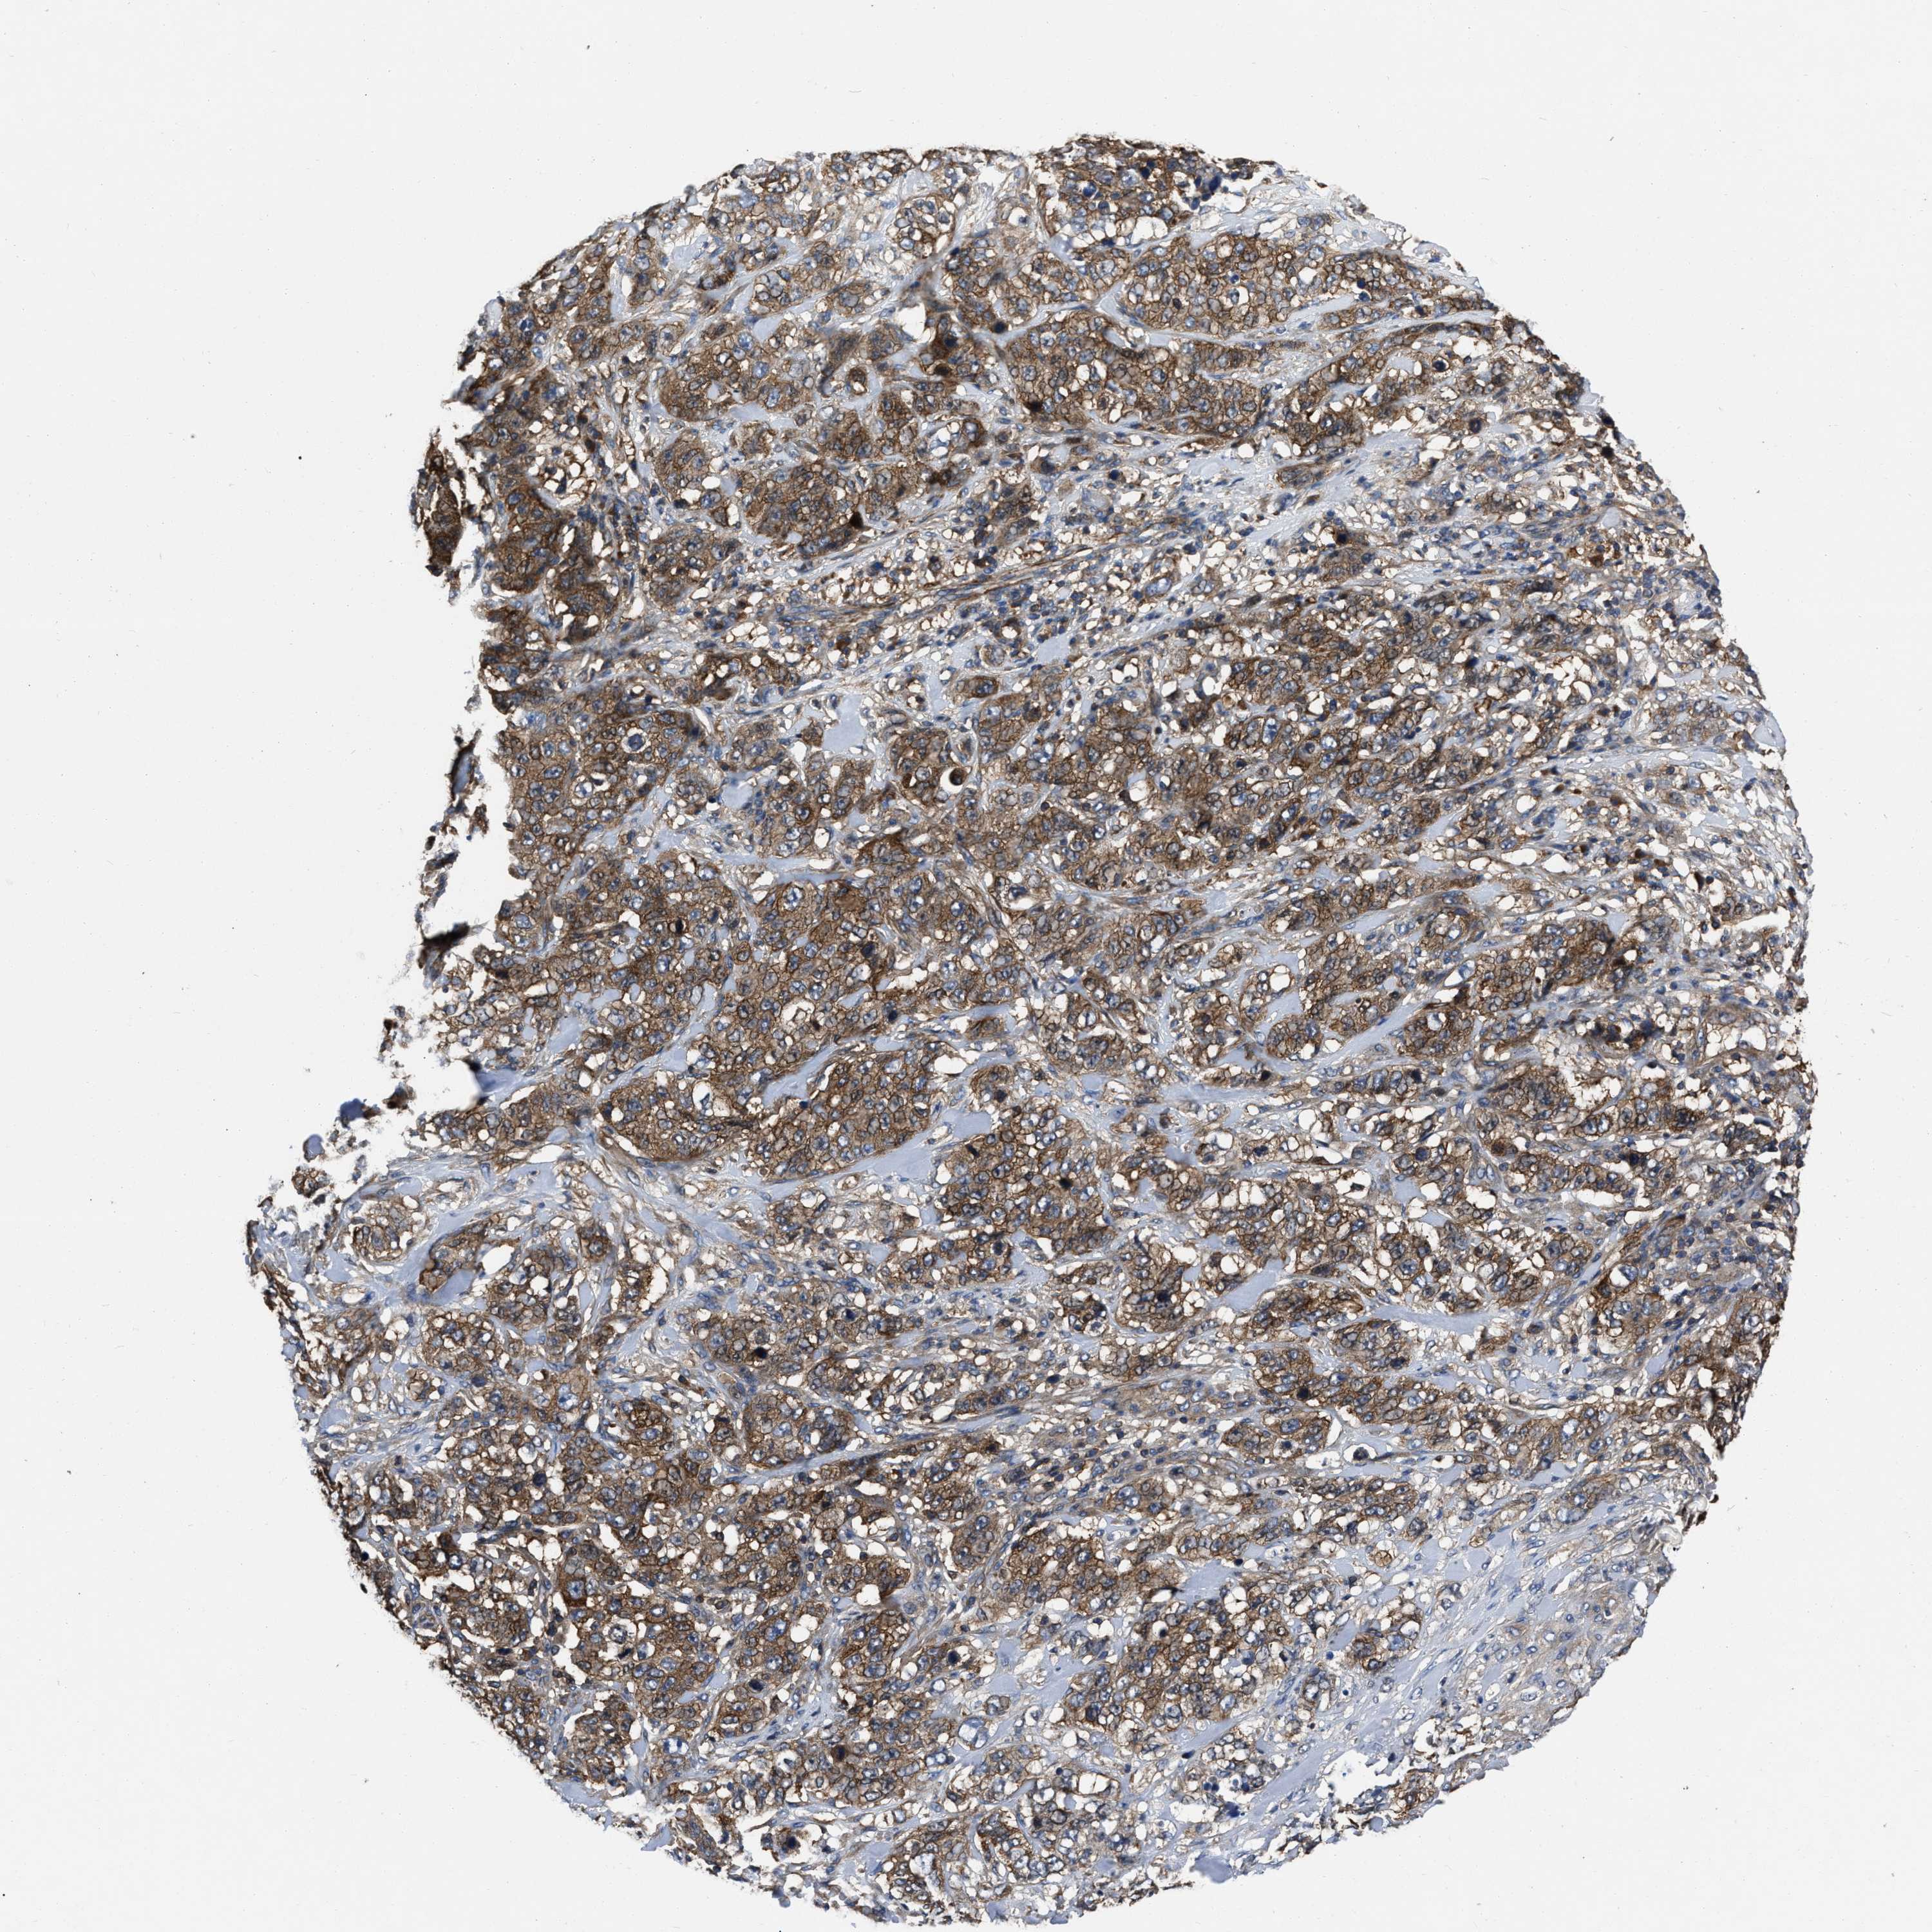

STOMACH CANCER - Protein expressioni

A mouse-over function shows sample information and annotation data. Click on an image to view it in a full screen mode. Samples can be filtered based on level of antibody staining by selecting one or several of the following categories: high, medium, low and not detected. The assay and annotation is described here.

Note that samples used for immunohistochemistry by the Human Protein Atlas do not correspond to samples in the TCGA dataset.

Antibody stainingi

Antibody staining in the annotated cell types in the current human tissue is reported as not detected, low, medium, or high, based on conventional immunohistochemistry profiling in selected tissues. This score is based on the combination of the staining intensity and fraction of stained cells.

Each image is clickable and will lead to virtual microscopy that enables deeper exploration of all samples and also displays staining intensity scores, fraction scores and subcellular localization as well as patient and tissue information for each sample.

Antibody HPA017936

Antibody HPA018950

Antibody HPA018954

Staining

High

Medium

Low

Not detected

Intensity

Strong

Moderate

Weak

Negative

Quantity

>75%

75%-25%

<25%

None

Location

Nuclear

Cytoplasmic/membranous

Cytoplasmic/membranous,nuclear

Adenocarcinoma, NOS